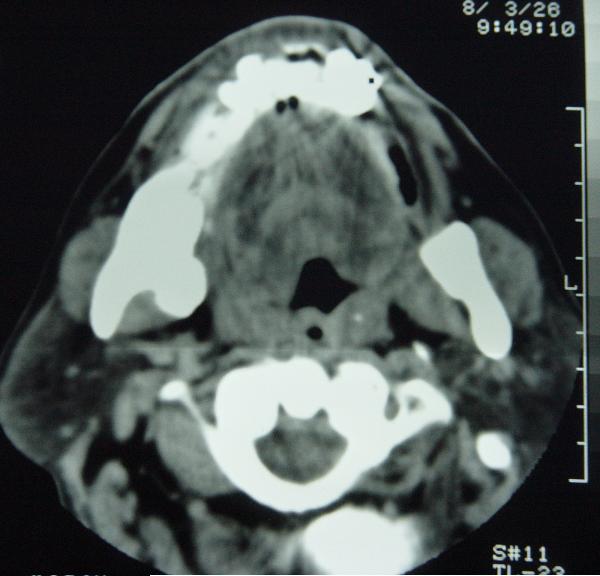

标题: CT12465:下颌骨肿瘤,请会诊 [打印本页]

标题: CT12465:下颌骨肿瘤,请会诊

发现下颌骨肿瘤近30年.逐渐增大.

位置及病程较长考虑:造粙细胞瘤

造釉细胞瘤?

考虑造釉c瘤

考虑右侧下颌骨水平部及升部骨纤维异常增殖症可能性大。